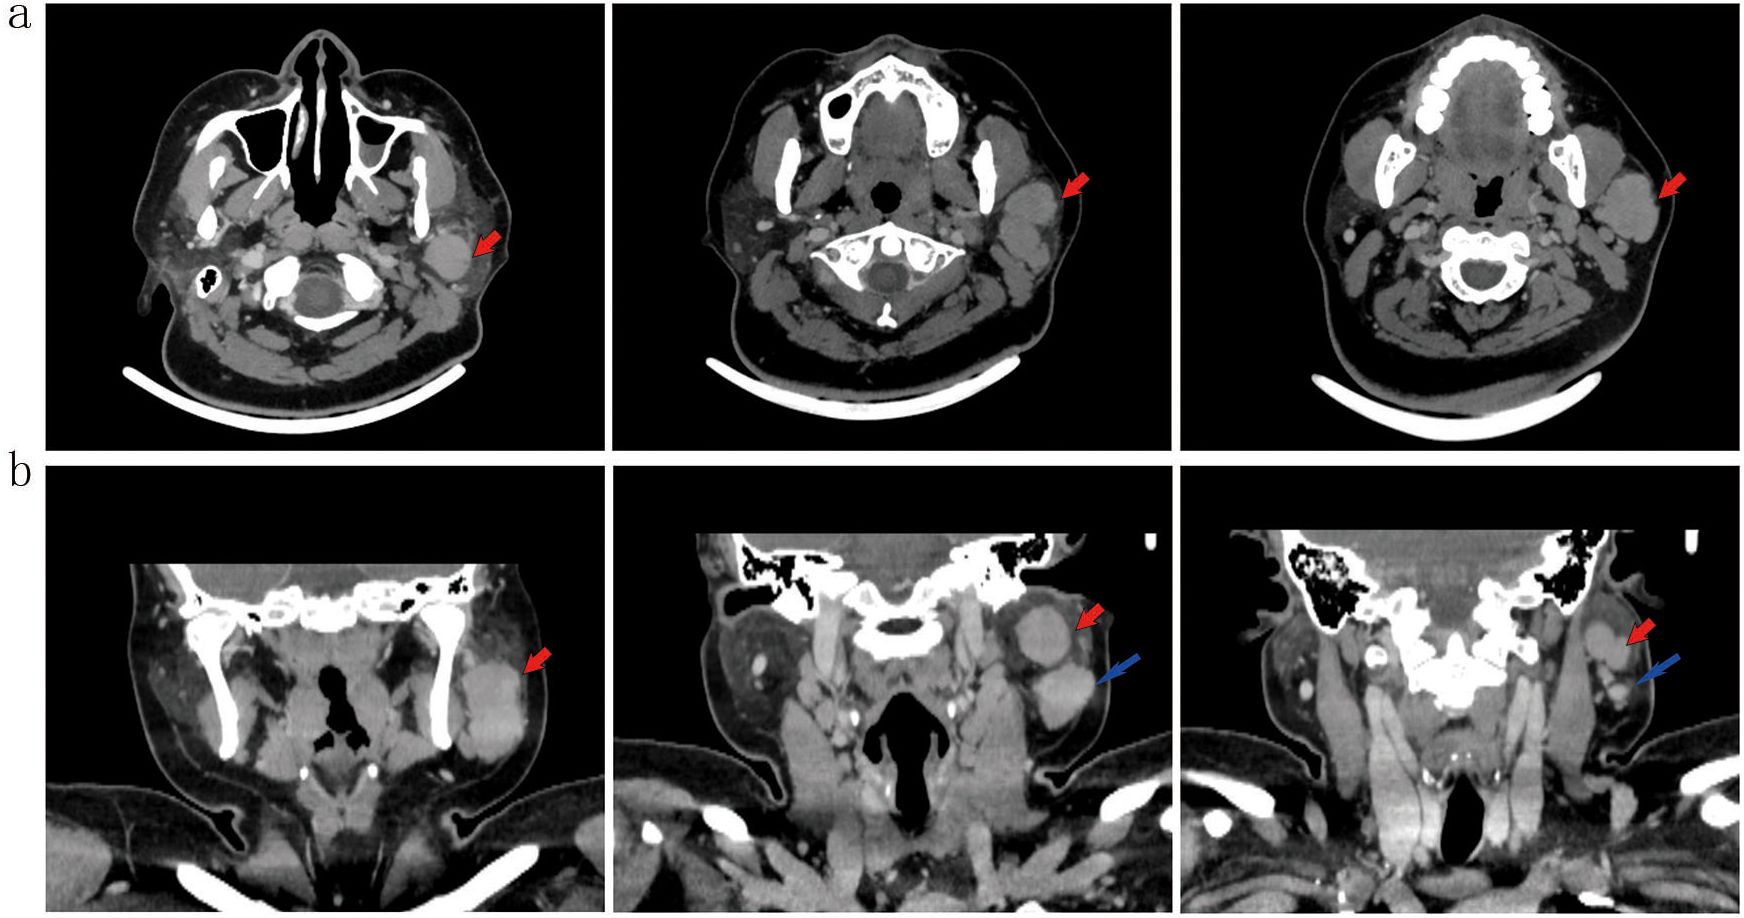

Background: Sebaceous lymphadenocarcinoma (SLAC) represents an extremely rare parotid malignancy, hypothesized to originate through malignant transformation of sebaceous lymphadenoma. To date, fewer than ten histopathologically confirmed cases have been documented globally. Case summary: A 33-year-old female presented with a persistent, painless left parotid mass that persisted despite anti-infective therapy. The patient underwent a comprehensive diagnostic workup prior to surgical resection. Histopathological examination of the specimen revealed sebaceous lymphadenoma with distinct foci of malignant transformation to SLAC, confirming a localized malignant process. Based on a review of the literature, this case represents the eighth reported instance of SLAC and the third with pathologically confirmed lymph node metastasis. Conclusion: SLAC most commonly presents as a painless parotid mass. Surgical resection is the cornerstone of therapy, with individualized use of radiotherapy. While early outcomes may be favorable, long-term surveillance is essential. International collaboration is urgently needed to establish registries and define standardized management guidelines for this exceedingly rare malignancy.